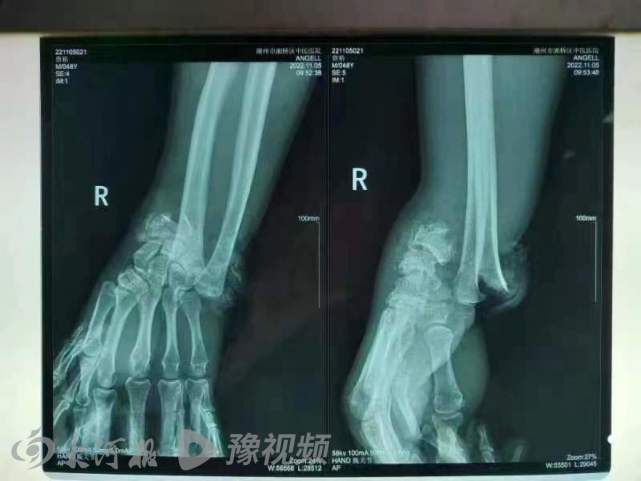

三轮车驾驶员X光片

据小詹介绍,事故造成2人身亡3人受伤。3名伤者中,他父亲2根肋骨骨折,腿部受伤;其余2名伤者,一人并无大碍,另一名伤势较重的是骑三轮车的驾驶员,大腿、手等多处部位受伤,需要手术。